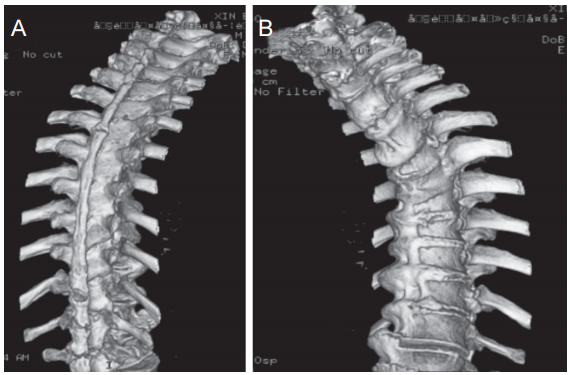

入院后给予口服普瑞巴林、盐酸曲马多缓释片、静脉滴注牛痘疫苗接种家兔炎症皮肤提取物(神经妥乐平),并行胸脊神经根阻滞术,疼痛无明显缓解。遂尝试行短时程经皮CL植入 SCS,因穿刺路径存在黄韧带骨化、椎板间隙融合,术中反复尝试不同节段椎板间隙穿刺甚至对侧穿刺均未成功,后改行胸脊神经根(右侧 T6~T8)射频热凝术,术后痛觉超敏较前缓解,但持续性疼痛仍存在,以夜间为著。进一步完善HLA-B27及骶髂关节CT排除强直性脊柱炎,完善胸椎CT(见图4),结合胸椎X线片检查结果,提示该病人合并DISH。病人要求再次行SCS,经科室讨论后决定采用内镜直视下CL植入SCS。

图4 胸椎三维CT

(A) 胸椎三维CT 背侧;(B) 胸椎三维CT腹侧